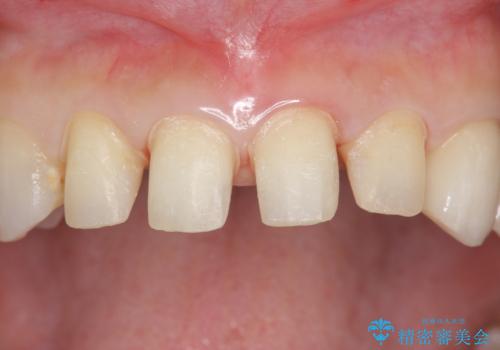

つぎはぎの前歯をセラミックにしたい

- 保険治療のプラスチックでつぎはぎの歯をセラミックにし、一緒に前歯の並びもきれいにしたいとのご希望でした。

特に裏側のつぎはぎ、二次う蝕(治したところの境目からの虫歯)が多く、審美目的だけでなく、虫歯の治療としても意味があったと思います。

色や形については納得いくまで修正し、最後は満足されていました。